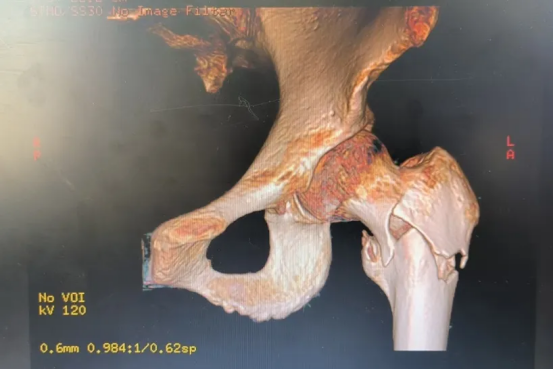

95岁的夏爷爷和80多岁的陈爷爷、王奶奶(均为化名)均因意外摔倒导致髋部剧痛、无法行走,被家人紧急送至我院骨关节科就诊。经详细检查,三位老人被诊断为“股骨粗隆间骨折”,还合并其他基础疾病。这种骨折被称为"人生最后一次骨折",对高龄患者而言尤为危险。

在传统观念中,高龄老人发生骨折,又合并多种基础疾病,往往被认为无法耐受手术,只能长期卧床保守治疗。然而,对于这三位老人和他们的家人而言,选择手术是一次“再拼一把”的努力,更是争取重新站立、重获生活质量的希望。

“面对高龄股骨粗隆间骨折患者,我们必须全面考虑:老人能否耐受麻醉?手术风险如何控制?术后能否真正恢复行走?”重庆郭昌毕中医骨伤医院关节科主任、副主任医师谭季镰表示,为这类患者实施手术需连克三大难关:基础疾病多、麻醉风险高;骨质疏松显著、手术操作复杂;术后康复缓慢、并发症发生率高。